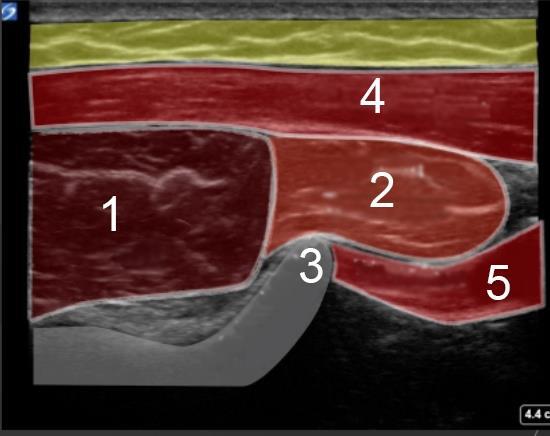

1. Infraspinatus: Transverse

2. Teres Minor: Transverse

3. Inferior Glenoid Tubercle of the Scapula

4. Posterior Deltoid

5. Triceps Tendon Long Head